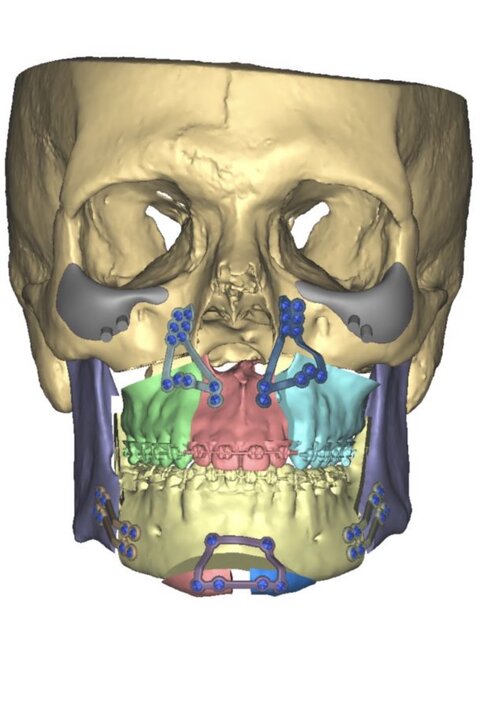

im getting surgery(trimax and infras) soon, any thoughts on this?my left side (the 31 mm) is also less wide in real life, i think would be good to extend it more to the nose area.